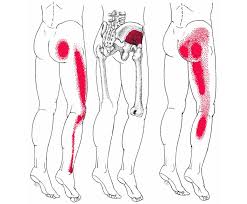

Download Sciatic nerve pain pictures